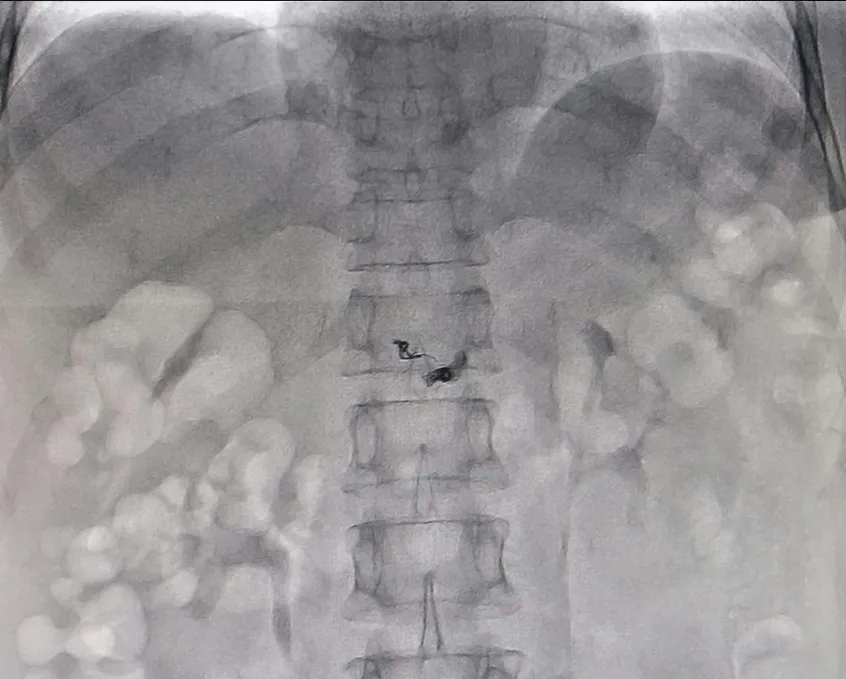

Các bác sĩ thực hiện can thiệp gây tắc lỗ dò. Ảnh: CTV

Các BS đã chụp kỹ thuật số xóa nền (DSA). Kết quả hình ảnh xác định bà T. bị Hemangioma ở tụy, kèm theo rò động mạch tụy lưng vào tĩnh mạch cửa. Sau đó, các BS khoa Ngoại tổng quát và Trung tâm Can thiệp tim mạch quyết định can thiệp điều trị cho bà T. bằng DSA, can thiệp nội mạch gây tắc mạch nuôi u bằng hạt P.V.A. Sau bốn giờ can thiệp, vùng tổn thương đã được khắc phục hoàn toàn. Sức khỏe bà T. dần ổn định.